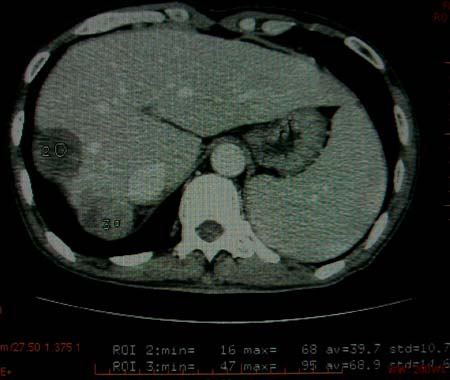

标题: CT16292:男,53岁,上腹部不适2月,B超发现肝内占位病变。 [打印本页]

标题: CT16292:男,53岁,上腹部不适2月,B超发现肝内占位病变。

符合肝ca增强,\"快进快出\";肝叶比例失常,右叶萎缩,肝裂增宽,脾大,肝硬化可能.

肝脏体积变小,肝裂增宽,分布异常,肝尾叶增大,脾肿大,考虑肝硬化可能性大,右肝病灶呈现早期充盈,延迟强化考虑肝内胆管细胞癌可能,不除外血管瘤

肝叶比例失调,左叶增大,肝裂增宽,脾脏增大,门脉增宽,肝右叶包膜下多发结节样阴影,增强虽说强化幅度不大,但还是符合快进快出特点;考虑肝硬化、脾大、结节型肝癌。胆管细胞癌多有延时强化、肝包膜凹陷征、周围胆管扩张等特点,本例明显不符;故不考虑。